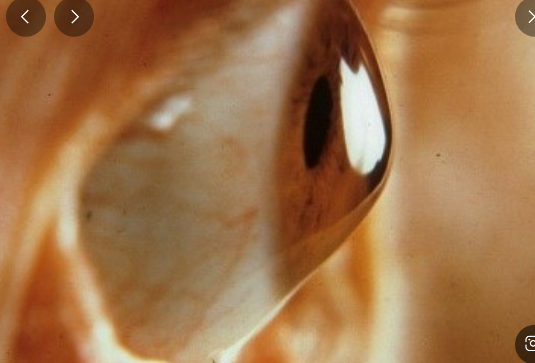

원추각막은 각막이 원뿔 모양으로 변형되어 발생하는 시력장애입니다. 각막은 눈의 앞부분을 덮고 있는 투명한 조직이며, 빛을 굴절시켜 망막에 상을 맺게 하는 역할을 합니다. 원추각막이 발생하면 각막이 비정상적으로 얇아지면서 돌출되어 부정난시가 발생하는 진행성 질환입니다.

5) 각막수종

각막수종은 수주에서 수개월 지속되고 대개 서서히 줄어들어 흉터로 대체되어 영구적인 시력 저하를 유발합니다.